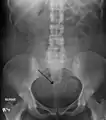

The presence of a uterine fibroid versus an adnexal tumor is made. Fibroids can be mistaken for ovarian neoplasms. An uncommon tumor which may be mistaken for a fibroid is Sarcoma botryoides. It is more common in children and adolescents. Like a fibroid, it can also protrude from the vagina and is distinguished from fibroids.[7] While palpation used in a pelvic examination can typically identify the presence of larger fibroids, gynecologic ultrasonography (ultrasound) has evolved as the standard tool to evaluate the uterus for fibroids. Sonography will depict the fibroids as focal masses with a heterogeneous texture, which usually cause shadowing of the ultrasound beam. The location can be determined and dimensions of the lesion measured. Also, magnetic resonance imaging (MRI) can be used to define the depiction of the size and location of the fibroids within the uterus.

A very large (9 cm) fibroid of the uterus which is causing pelvic congestion syndrome as seen on CT